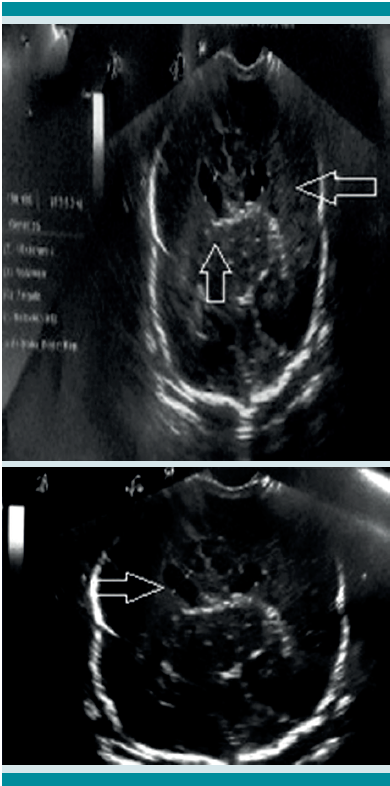

Durante su estancia se le practicó ultrasonido transfontanelar que reportó cuernos anteriores de ventrículos laterales dilatados sin imágenes patológicas intraventriculares; el resto del sistema ventricular se apreciaba sin alteración. Se realizó un ultrasonido abdominal para descartar otras malformaciones intra-abdominales que reportó: hígado, vesícula biliar, páncreas y bazo con tamaño y morfología dentro de los parámetros adecuados. Los ultrasonidos renal y de las vías urinarias mostraron aumento de volumen de ambos riñones con múltiples formaciones quísticas en todo el parénquima renal en relación con displasia renal multiquística bilateral (Figura 3).